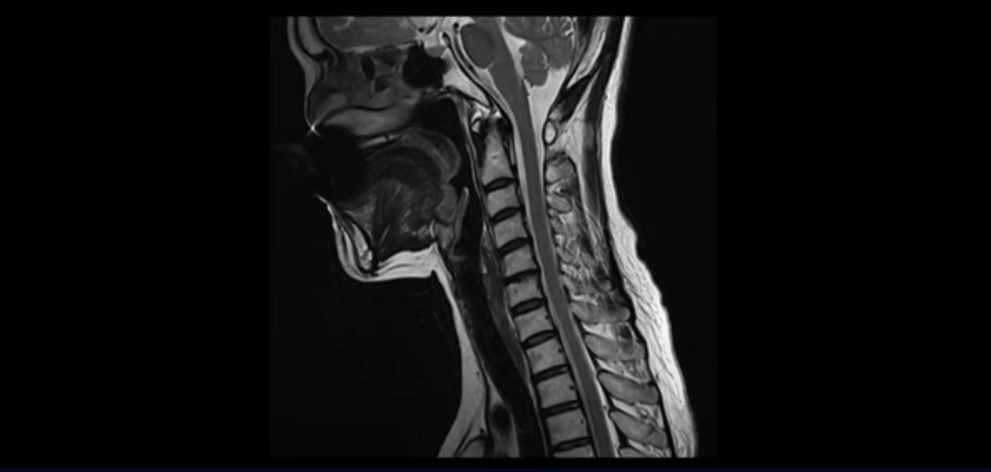

이분 MRI를 보실까요? 일자목에 머리가 앞으로 밀려 나간 거북목 체형입니다.

50대 후반에 근육이 많이 줄어들고 약해진 여성 환자들에게서 많이 보이는 체형입니다. 거북목에 등은 굽어있고 어깨도 앞으로 말려 있으면 등 근육과 뒷목 근육이 머리를 붙잡고 있느라 긴장되고 뭉치고 아플 수밖에 없습니다. 게다가 이분 근육을 검사했더니 놀랍게도 근감소증이 나왔습니다. 근육량도 기준보다 훨씬 더 적은 겁니다. 그러니까 다른 환자들보다도 더 심하게 아프고 오랫동안 아플 수밖에 없는 겁니다.